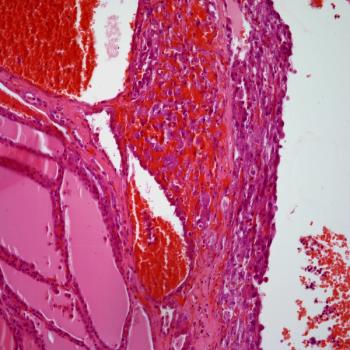

CT images from a 58-year-old female who underwent surgery for pancreatic cancer show a previously unseen structure. What is your diagnosis?